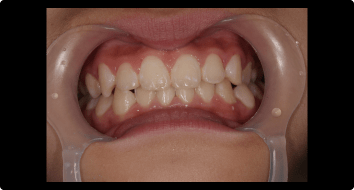

症例2:叢生の矯正治療

BEFORE

AFTER

症例概要

年代・性別

10歳代 女性

主訴

デコボコした歯並びを治したい

治療内容

ブラケット(ワイヤー)を用いた矯正治療

治療期間

4ヶ月

治療のリスク

定期検診、セルフケアを怠ると虫歯になる可能性があります

治療費用

440,000円(税込)